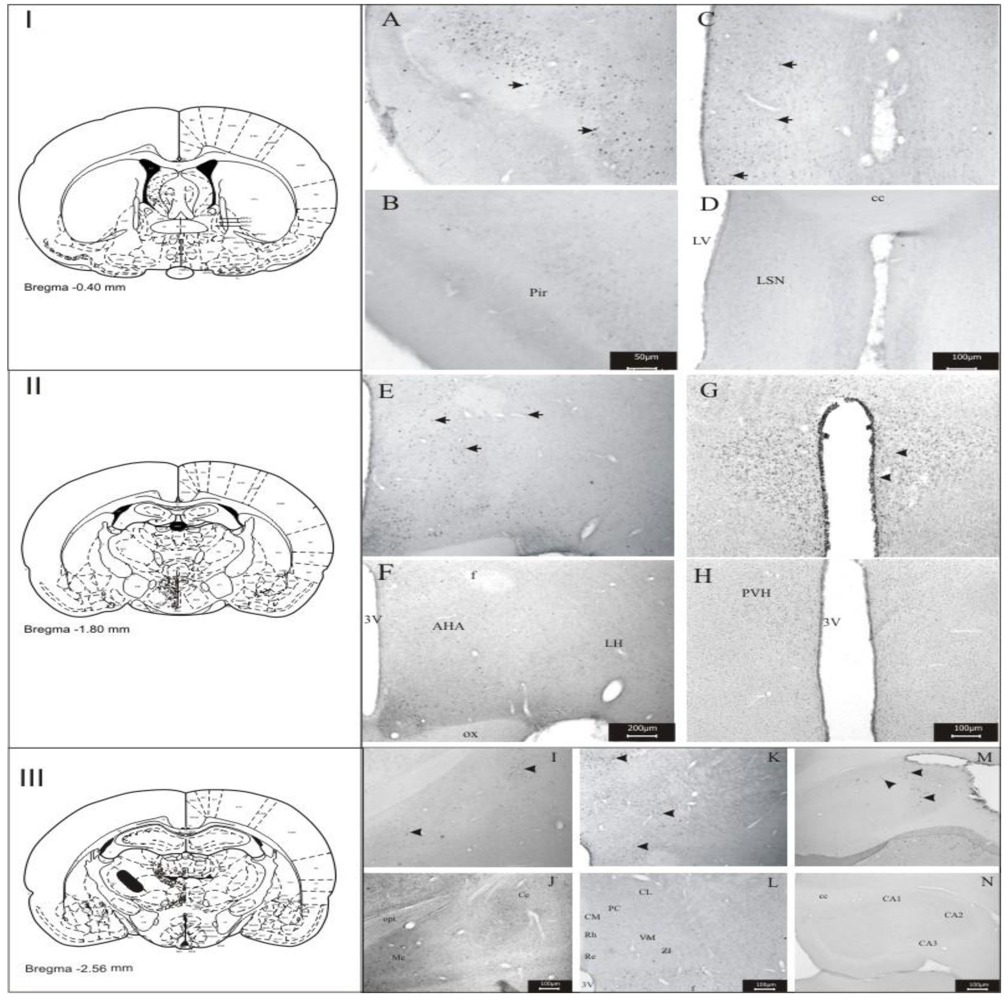

3.1. Imunohistochemistry Assays